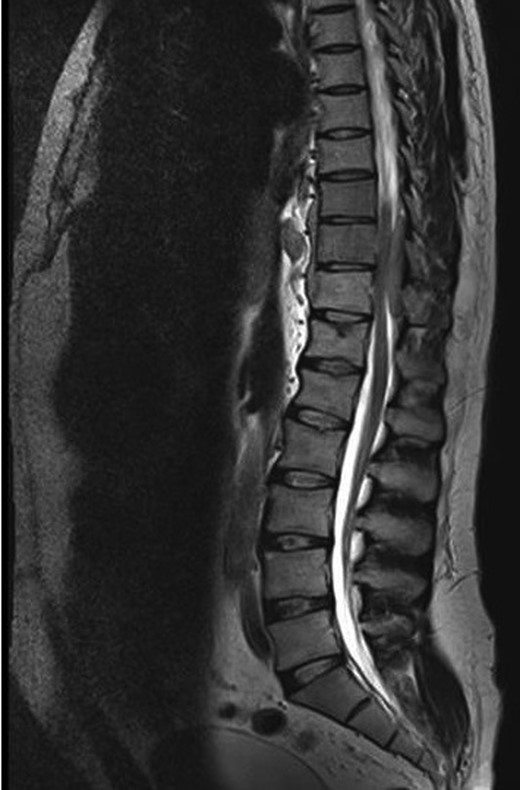

A 30-year-old male patient was admitted to our clinic with back pain. Pain was provoked by movements. The severity of pain was associated with the inability to perform the activities of daily living. The patient did not have any lymphoma-related B-type symptoms, including body weight loss, fever and sweat at night. He did not have a past and family history. There was no neurological deficit. Routine laboratory test results were normal. A magnetic resonance imaging (MRI) scan of the thoracic spine demonstrated an epidural tumor at the T9–11 level (Figs 1–3). The patient underwent spinal cord decompression via total laminectomy of T9–11 levels. Subtotal resection of the tumor was performed. Histological examination revealed the polymorphous cellular infiltration by histiocytes, large mononuclear cells and lacunar Reed–Sternberg cells with folded multi-lobed nuclei and small nucleoli (Fig. 4). Immunohistochemical staining was positive for CD15 and CD30 and negative for CD3, CD20, CD79a or CD45Ro. These features were most frequently observed in the mixed cellularity type of Hodgkin's lymphoma. Histological examination of the vertrebral body revealed no abnormality. The results of all other examinations (F-18 fluorodeoxyglucose positron emission tomography (F-18 FDG PET/CT), bone marrow biopsy and computed tomography (CT) of the chest, abdomen and pelvis) were negative for an occult disease. The patient was referred to the hematology department to undergo staged treatment. Six courses of chemotheraphy containing ABVD regimen (adriamycin, bleomycin, vinblastine and dacarbazine) were given to the patient. Postoperative MRI scan did not reveal any evidence of Hodgkin's disease (Fig. 5), F-18 FDG PET/CT, CT of the chest, abdomen and pelvis were obtained in 24 months and did not reveal any evidence of Hodgkin's disease.